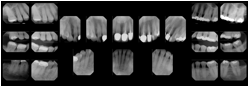

3. A dental provider wishes to capture a series of DICOM IO images for the patient’s dentition. The tooth morphology, teeth are divided into molars, premolars, canines and incisors, and a number of images for each jaw. The anatomic information was captured utilizing the triplet of schema. This standard code sequence is based on ISO 3950-2010, Dentistry - Designation system for teeth and areas of the oral cavity.

Every IO image should have anatomic information either through the primary or modifier sequence.

In most standard cases, images are oriented in structured layouts. These structured displays are useful to be shared between providers for reference purposes.

Table OO.1.1-1 shows structured display standard templates, where Viewset ID is based on the Japanese Society for Oral and Maxillofacial Radiology (JSOMR) classification provided by JIRA (Japan Medical Imaging and Radiological Systems Industries Association, www.jira-net.or.jp). Expected or typical teeth to be imaged location, region and designation codes are based on ISO 3950-2010, Dentistry - Designation system for teeth and areas of the oral cavity. For all the hanging protocols listed in OO.1.1-1, the value to use for Hanging Protocol Creator (0072,0008) is "JSOMR" and the value to use for Hanging Protocol Name (0072,0002) does not include "JSOMR" (e.g., "DL-S001A", not "JSOMR DL-S001A").